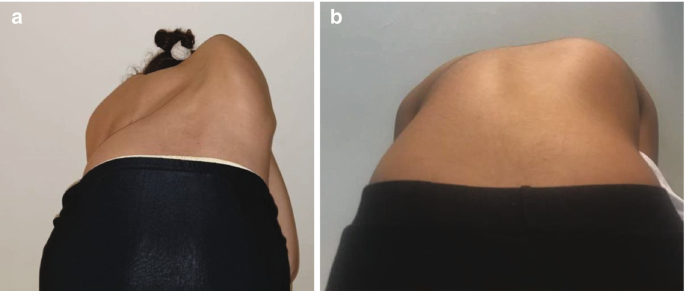

4. الدوران الفقري قبل العلاج

الدوران الفقري هو أحد أكثر مكونات الجنف تعقيدًا.

الدوران الصدري الأقل قبل العلاج يرتبط بنتائج أفضل

خاصة عند الأطفال الذين لديهم قفص صدري أفقي

لذلك، لا تعتمد التقييمات الحديثة على زاوية كوب فقط، بل تشمل درجة الدوران أيضًا.

6. الشكل المحوري للعمود الفقري

عند النظر للعمود الفقري من الأعلى، يمكن أن يكون:

على شكل S

أو على شكل V

هذا الاختلاف يؤثر على كيفية توزيع الضغط داخل الحزام، وبالتالي على فعالية العلاج.

ومن هنا تأتي أهمية تصميم الحزام بشكل فردي لكل طفل.